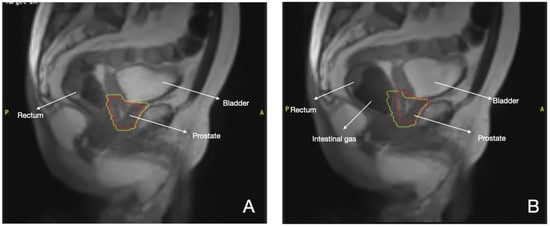

3.1. Prostate Cancer

- Intven, M.; Otterloo, S.d.M.v.; Mook, S.; Doornaert, P.; Breugel, E.d.G.-V.; Sikkes, G.; Willemsen-Bosman, M.; van Zijp, H.; Tijssen, R. Online adaptive MR-guided radiotherapy for rectal cancer; feasibility of the workflow on a 1.5T MR-linac: Clinical implementation and initial experience. Radiother. Oncol. 2020, 154, 172–178. [Google Scholar] [CrossRef]